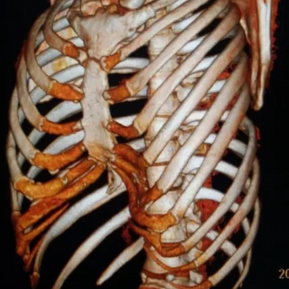

The anterior chest wall exhibits an obvious depression, causing severe compression and displacement of the heart to the left thoracic cavity. The Haller index is notably high at 5.6.

During the surgery, a 2 cm incision was made on each side of the chest wall, followed by a third 2 cm incision below the xiphoid process. After thorough pre-shaping of the bone structure at the depression, two bars were inserted to correct the deformity. After the surgery, the deformity was completely resolved, and the chest wall returned to its normal appearance.